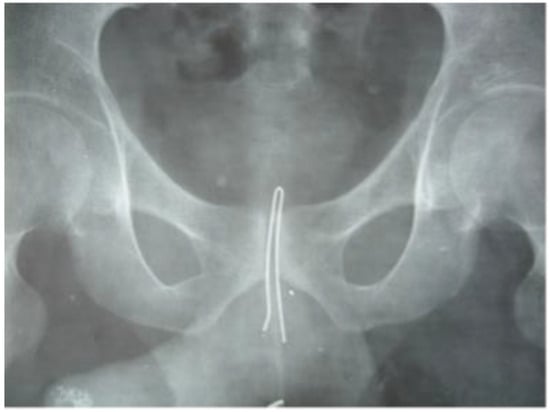

| 8 | 61 | M | pen cartridge | urethra | unknown | unknown | LUTS | cystoscopy |